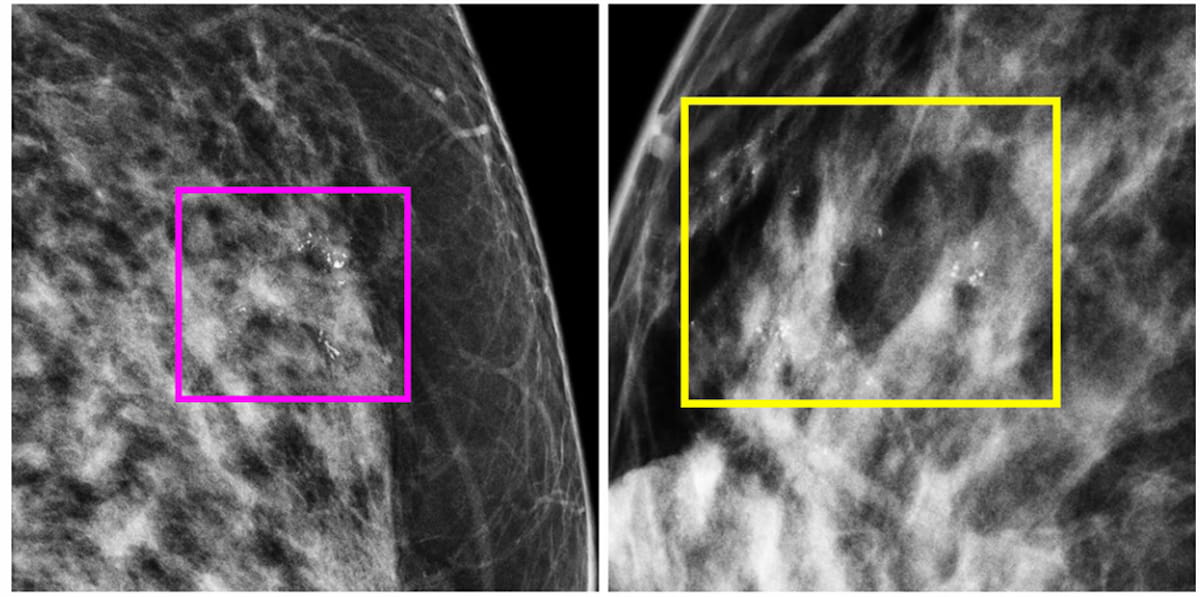

A model combining deep learning features and clinical variables demonstrated a 30 percent higher AUC than a clinical model for detecting DCIS and invasive ductal carcinoma from suspicious microcalcifications on mammography, according to a new study.